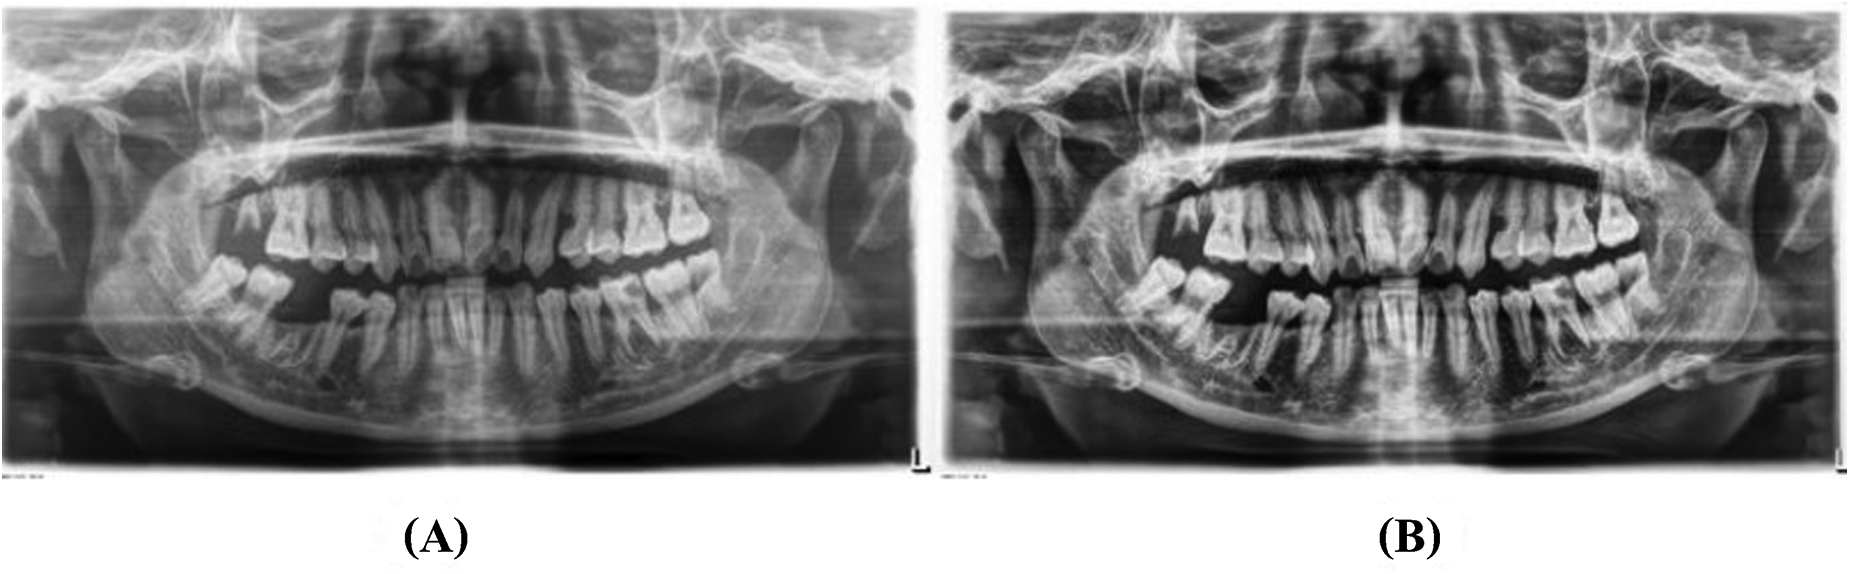

Labeling of the images was performed using the LabelMe tool for object segmentation and Labelme2yolo for data conversion. Annotations focused on the cemento-enamel junction (CEJ) and the alveolar bone crest (20) (Figure 4). Recognizing the critical role of labeled data in supervised machine learning, this research utilized LabelMe for object segmentation and Labelme2yolo to convert the data into a format ready for training.

Figure 4

Image showing the distance between the CEJ and the alveolar bone crest (A) and teeth (B), labeled using LabelMe.